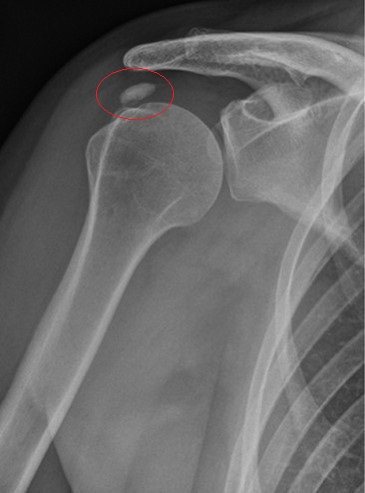

Fortgeschrittener Verschleiß, die sogenannte Omarthrose, ist eine häufige Ursache für Gelenkschmerzen in der Schulter. Diese entsteht durch die Abnutzung des Knorpels, der als Schmiermittel zwischen dem Oberarmknochen und der Schultergelenkpfanne dient. Wird dieser natürliche „Stoßdämpfer“ immer weiter abgebaut, können die Knochen aufeinandertreffen und Schmerzen verursachen.

Um festzustellen, ob eine fortgeschrittene Omarthrose die Ursache für Schulterschmerzen ist und um die Gelenksituation im Vorfeld einer Behandlung einschätzen zu können, werden verschiedene Bildgebende Verfahren zu Rate gezogen. Zur Abbildung der knöchernen Struktur des Schultergelenks ist die Röntgendiagnostik das Mittel der Wahl. Weichteile wie Sehnen und Schleimbeutel werden hingegen mittels eines Ultraschallgerätes beziehungsweiser eines MRT sichtbar.